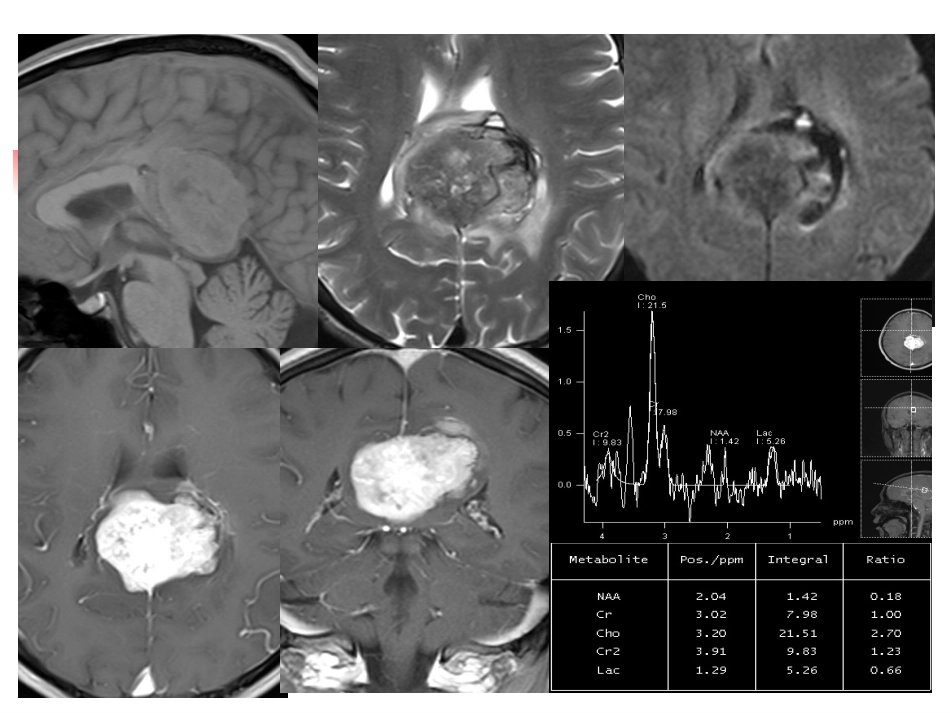

病理结果:<胼胝体镰旁>孤立性纤维性肿瘤/血管周细胞瘤(SFT/HPC)。免疫组化:GFAP(-)、CD99(+)、bcl-2(+)、CD34(+)、S-100(-)、Ki-67(80%)、Claudin-1(+)、EMA(-)、PR(-)。颅内孤立性纤维瘤MRI诊断(solitaryfibroustumors,SFT)大坪医院放射科-lch颅内孤立性纤维瘤概述1临床及病理2MRI表现3鉴别诊断4一一概述概述DFT是一种临床上罕见肿瘤。本科室2010-2015总共4例(201007843;100381936;200253143;200246110)。SFT现一致认为是间质源性肿瘤,起源于树突状间质细胞。该肿瘤1931年由Klemperer和Rabin首先命名。原发于中枢神经系统(CNS)的SFT于1996年被Carneiro等首次报道,其将这类发生于脑膜的SFT与脑膜瘤、血管周细胞瘤在形态学及免疫组化上进行了区别。概述概述常见发生部位:以胸膜最常见。胸膜外SFT:除胸膜腔外,其他的好发部位有上呼吸道、眼眶、腹腔和肢体软组织,也有发生在口腔、头面部、咽喉部、中枢神经系统、纵隔、肝脏、肺、肾脏、膀胱、甲状腺及输卵管等处。概述发生于颅内较少见。颅内常见发生部位:后颅窝和脊髓。1996年首次报道发生于脑膜的SFT。2007年WHO中枢神经系统肿瘤分类将其归为脑膜间叶组织肿瘤(WHOI级)。二二临床及病理临床及病理SFT发病年龄为19~85岁,发病高峰在40~60岁之间,女性略多见。临床上常无症状,多见于中年人,没有性别差异,通常表现为缓慢生长的肿块。临床表现上与肿瘤的大小、部位、良恶性有关,主要为肿瘤占位症状和颅内高压。临床及病理大体:SFT形态不规则,多数有包膜,界限清楚,常有蒂。多发者罕见。切面较坚硬、灰白色、常具有编织状、漩涡状外观。镜下:肿瘤细胞排列的典型表现为富细胞区和少细胞区共存,被纤维性间质分隔,具有血管外皮细胞瘤样分支状血管。富细胞区由梭形细胞构成,呈相互交织的短束状排列,形成“人”字或者席纹状排列。少细胞区可高度纤维化,或呈不常见的黏液样变。三三MRI表现国外文献研究发现,SFT的MRI表现具有其特异性,并将其作为区别其他肿瘤的重要依据。SFT因起源于成纤维细胞,镜下多以致密的梭形细胞为主,所以大部分学者认为其在MRI上信号与肌肉信号相似,T1、T2上多表现为等、稍低信号,而这种T2WI的低信号并在增强后显著强化被认为是颅内SFT的特征性表现;并且肿瘤可见粗大的流空血管。YCWeon,EYKim,HJKim,etal.ItracranialSolitaryFibrousTumors:ImagingFindingsin6ConsecutivePatients.AJNR,2007,9(28):1466-1470.而另一部分肿瘤表现为稍高、低混杂信号改变,被学者命名为特殊的“阴-阳”信号改变。其病理基础是胶原纤维部分对应的是T2低信号区域,而粘液变性区域及血管间质区域对应的是T2高信号区域。NawahiroH,NagakawaS,OsadaH,etal.Solitaryfibroustumoroftheminingesintheposteriorcranialfossa:magneticresonanceimagingandhistologicalcorrelation-casereport.NeurolMedChir,2007,7(47):269-272.实体型:典型表现为等T1、等或短T2为主混杂信号,增强扫描T2WI低信号区明显强化。多囊型:表现为多发囊状长T1、长T2信号病灶,增强扫描呈多囊环形强化。囊实型:具有实体型及多囊型信号特点。男性,48岁,发现肿瘤27天。病例1:(201007843)男性,63岁,无明显诱因下突发头痛伴左侧肢体无力8h。病理:(右侧额后部)孤立性纤维性肿瘤(低度恶性)病例2:(200246110)病变位于右额叶区,T1WI呈低信号,边界清楚,占位效应较明显,与脑膜关系密切病史:患者女性,56岁,记忆力下降1年。病理:<左颞枕部>梭形细胞肿瘤,细胞轻度异型,富于血管,结合免疫组化,考虑孤立性纤维性肿瘤(SFT)(低度恶性潜能)。病例3:(200253143)T1WIT2WIFLAIR增强病史:患者女性,44岁,头晕、头痛、消瘦1月。病理:<左枕叶及窦镰旁>梭形细胞肿瘤,结合免疫组化,形态符合孤立性纤维性肿瘤(低度恶性)。病例4:(100381936)四四鉴别诊断良性SFT尽管肿瘤巨大,坏死亦少见,即使出现坏死区,范围多较小。恶性SFT坏死相对多见,但坏死区范围亦较小。鉴别诊断:脑膜瘤其他间质来源肿瘤(如血管周细胞瘤)淋巴瘤病史:头痛10月,加重1月...